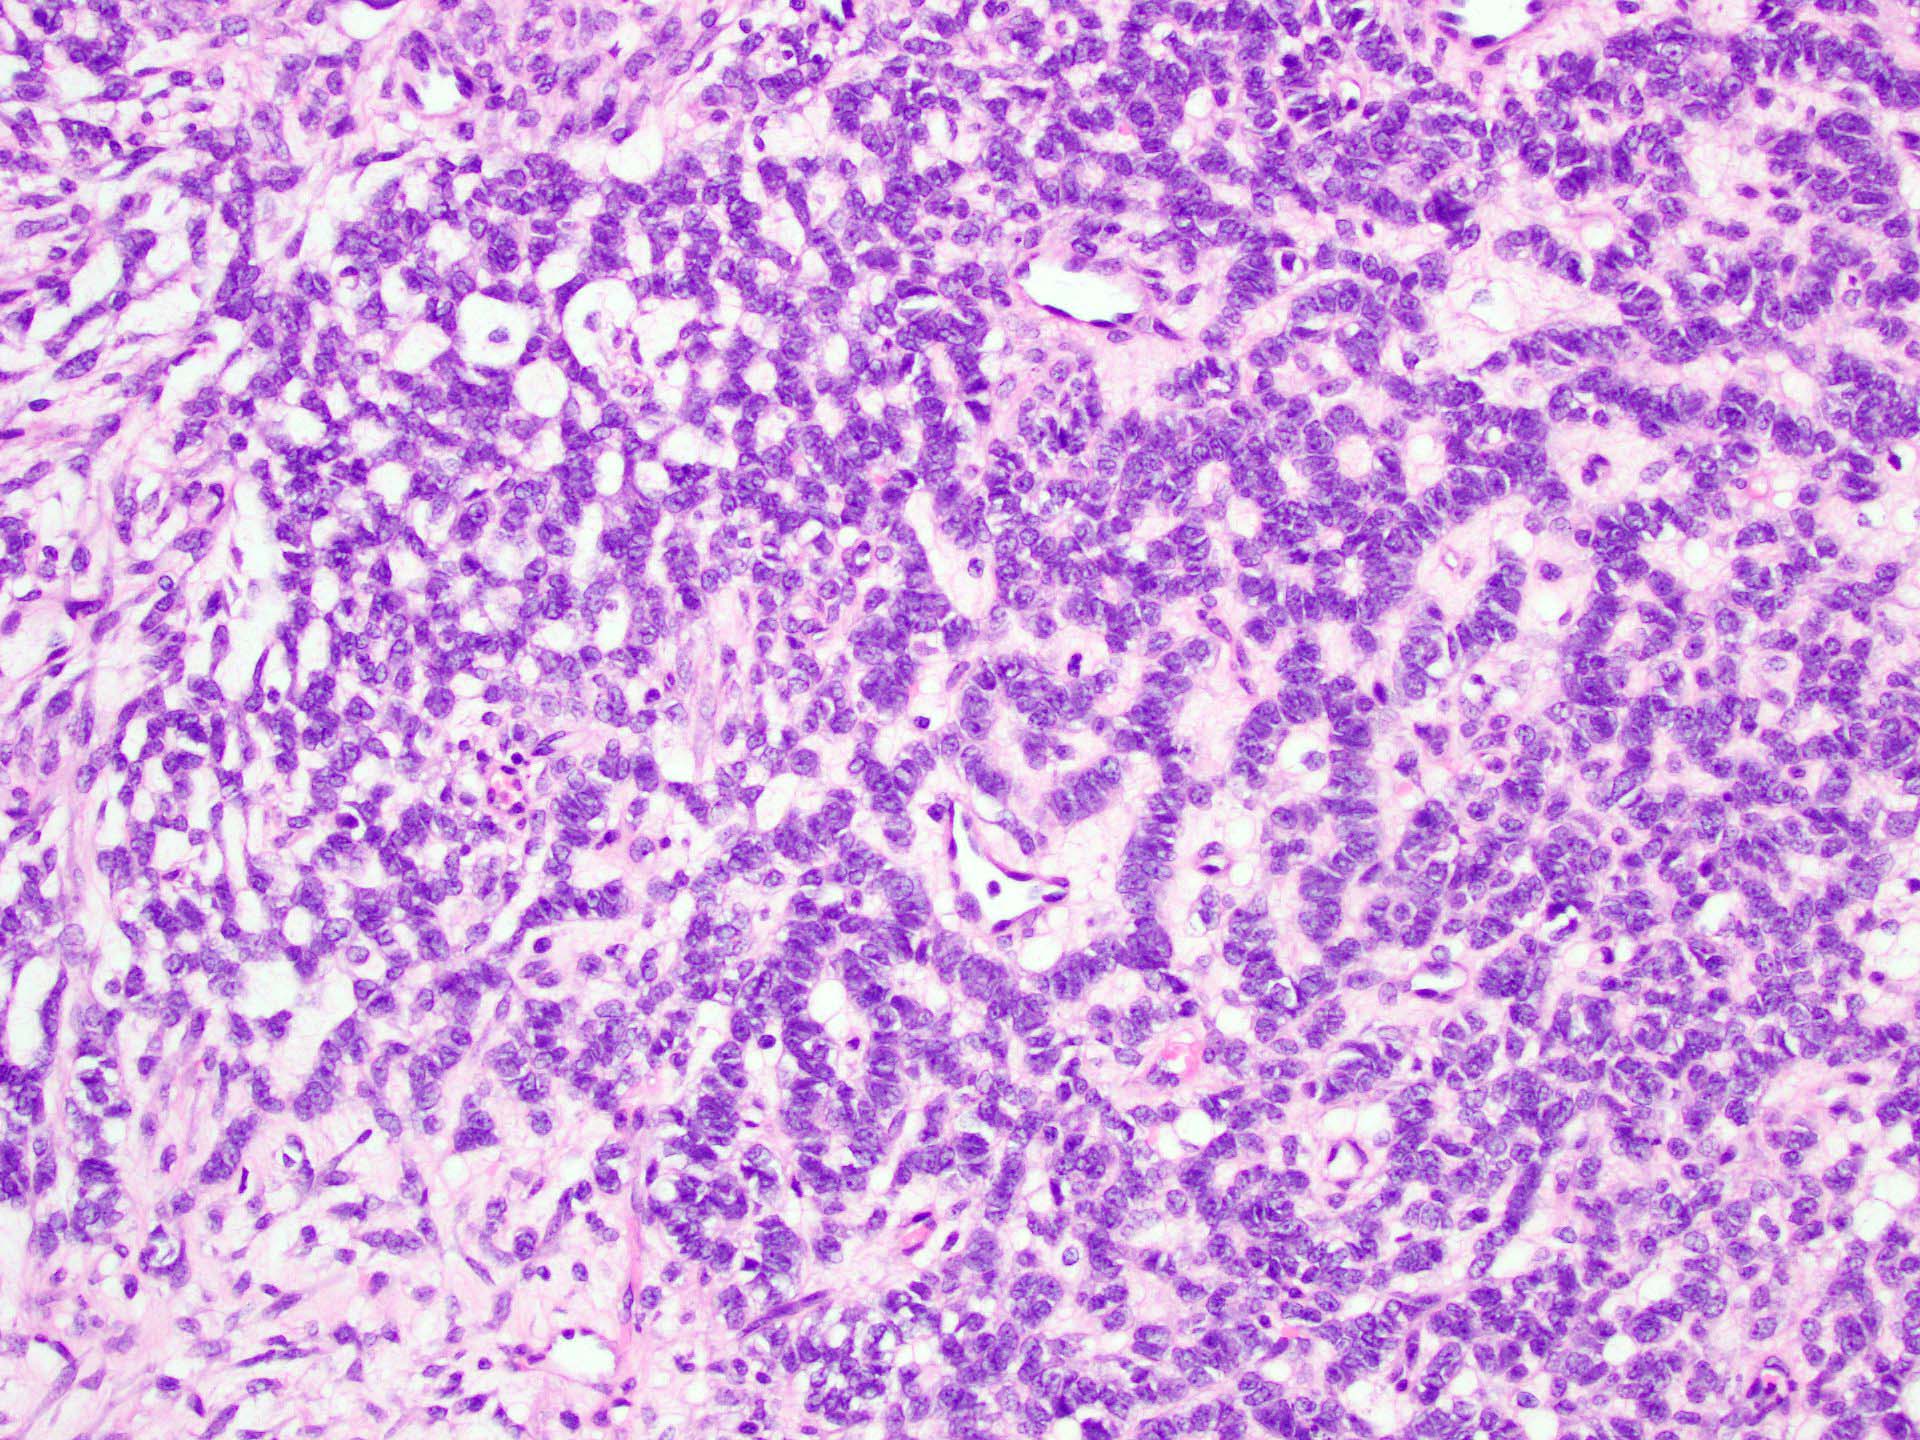

Microscopic (histologic) description

- Tubular pattern (most common and usually present at least focally) with solid or hollow tubules

- Cuboidal or columnar cells

- Bland oval to round, monotonous nuclei

- Pale cytoplasm

- Lipid rich or oxyphilic variants may be associated with Peutz-Jeghers syndrome

- Other patterns: trabecular, diffuse, alveolar, pseudopapillary, reniform, pseudoendometrioid, spindled

- Absent to very rare Leydig cells

- Pathologic features predictive of malignant behavior include 5 mitoses per 10 high power fields, severe cytologic atypia, necrosis and size > 5 cm

- Reference: Am J Surg Pathol 2005;29:143

Microscopic (histologic) images

A 40 year old woman is seen in the clinic with complaints of irregular uterine bleeding and pelvic fullness. Transvaginal ultrasound shows a 9 cm right ovarian mass. The mass is surgically removed and a pathologic examination shows the features in the picture above. The mass is positive for inhibin and SF1. The tumor is negative for EMA, PAX8, MelanA and chromogranin. In which of the following general categories does this tumor belong?

C. Pure sex cord tumor. Sertoli cell tumor is a pure sex cord neoplasm of the ovary composed of Sertoli cells most commonly arranged in a tubular pattern. Sertoli cells are positive for inhibin and SF1. Answer D is incorrect because no Leydig cells, which are positive for MelanA and are stromal in nature, are present. Answer B is incorrect because the tumor is negative for neuroendocrine markers. Answer A is incorrect because the tumor is negative for EMA and PAX8.